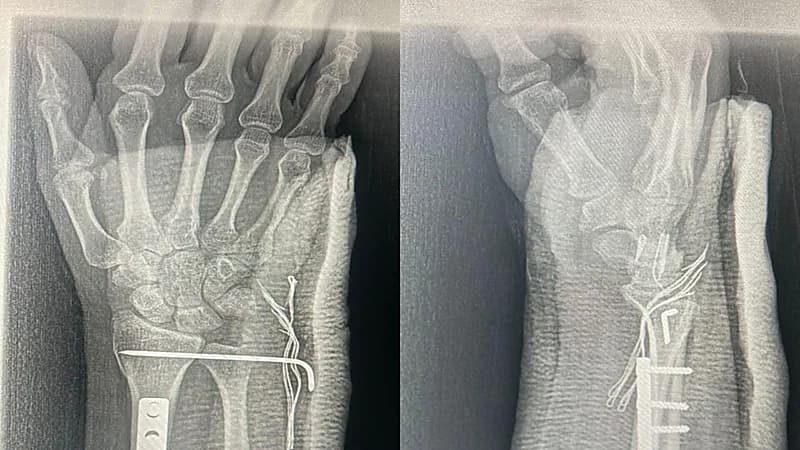

تَمكن فريق طبي في مستشفى تمير العام، عضو تجمع الرياض الصحي الثاني، من إجراء تثبيت لكسر في عظمتين، بتقنية التصوير الشعاعي باستخدام جهاز الكارم.

وأوضح المستشفى، أنه استقبل شابًّا يبلغ من العمر 29 عامًا تعرض للسقوط من دراجة نارية، وتبين بعد إجراء الفحوصات الأولية وجود إصابة في الساعد الأيمن، وتم نقله مباشرة إلى غرفة العمليات؛ حيث تم تثبيت كسر عظمتي الساعد باستخدام تقنية التصوير الشعاعي CARM الذي تم توفيره حديثًا، وهي العملية الأولى التي تُجرى في المستشفى بواسطة هذه التقنية.

وأفاد الفريق الطبي بأن العملية تكللت بالنجاح، وغادر المريض المستشفى بعد تلقيه الرعاية الطبية اللازمة، وتتم متابعته في العيادات الخارجية.

زيشار إلى أن الكادر الطبي الذي شارك في العملية يتكون من فريق العظام: الدكتور ديس عبدالله، والدكتور محمد أحمد، ومن التخدير الدكتورة زهراء تناح، ومن الأشعة الدكتور إبراهيم الحسين والدكتور فهد السلوم.